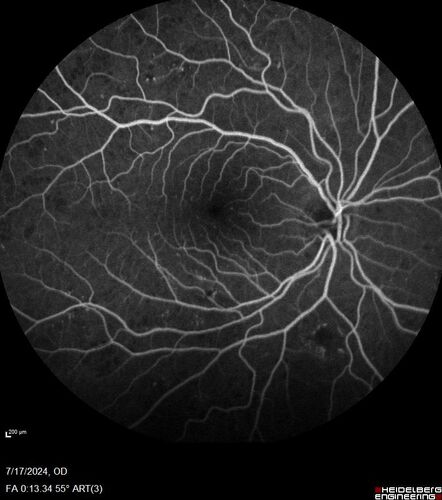

Bear tracks (and diabetic retinopathy)

48 year old female with bear tracks in her retina and NPDR.